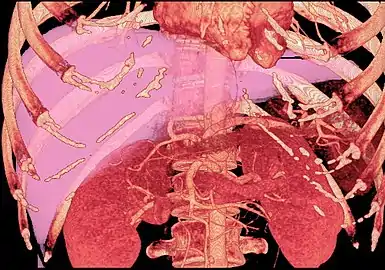

With the recent advances of noninvasive imaging, living liver donors usually have to undergo imaging examinations for liver anatomy to decide if the anatomy is feasible for donation. The evaluation is usually performed by multidetector row computed tomography (MDCT) and magnetic resonance imaging (MRI). MDCT is good in vascular anatomy and volumetry. MRI is used for biliary tree anatomy. Donors with very unusual vascular anatomy, which makes them unsuitable for donation, could be screened out to avoid unnecessary operations.

MDCT image. Arterial anatomy contraindicated for liver donation

MDCT image. 3D image created by MDCT can clearly visualize the liver, measure the liver volume, and plan the dissection plane to facilitate the liver transplantation procedure.